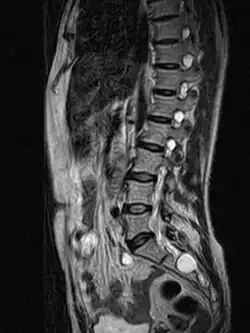

| MRI image showing a Tarlov cyst | |

MRI

MRI, or Magnetic Resonance Imaging, is considered the imaging study of choice in identifying Tarlov cysts. MRI provides better resolution of tissue density, absence of bone interference, multiplanar capabilities, and is noninvasive. Plain films may show bony erosion of the spinal canal or of the sacral foramina. On MRI pictures, the signal is the same as the CSF one.

Tarlov cysts are most commonly located in the S1 to S4/S5 region of the spinal canal, but can be found along any region of the spine. Tarlov cysts typically form on the extradural portions of the sacral nerve roots, most often near the dorsal root ganglion of the dorsal (sensory) nerve roots. They arise within the perineural space, between the endoneurium and perineurium. Occasionally, these cysts are observed in the lumbar and thoracic spine.[19] The cysts are often multiple, extending around the circumference of the nerve, and can enlarge over time to compress neighboring nerve roots, to cause bone erosion.[22]